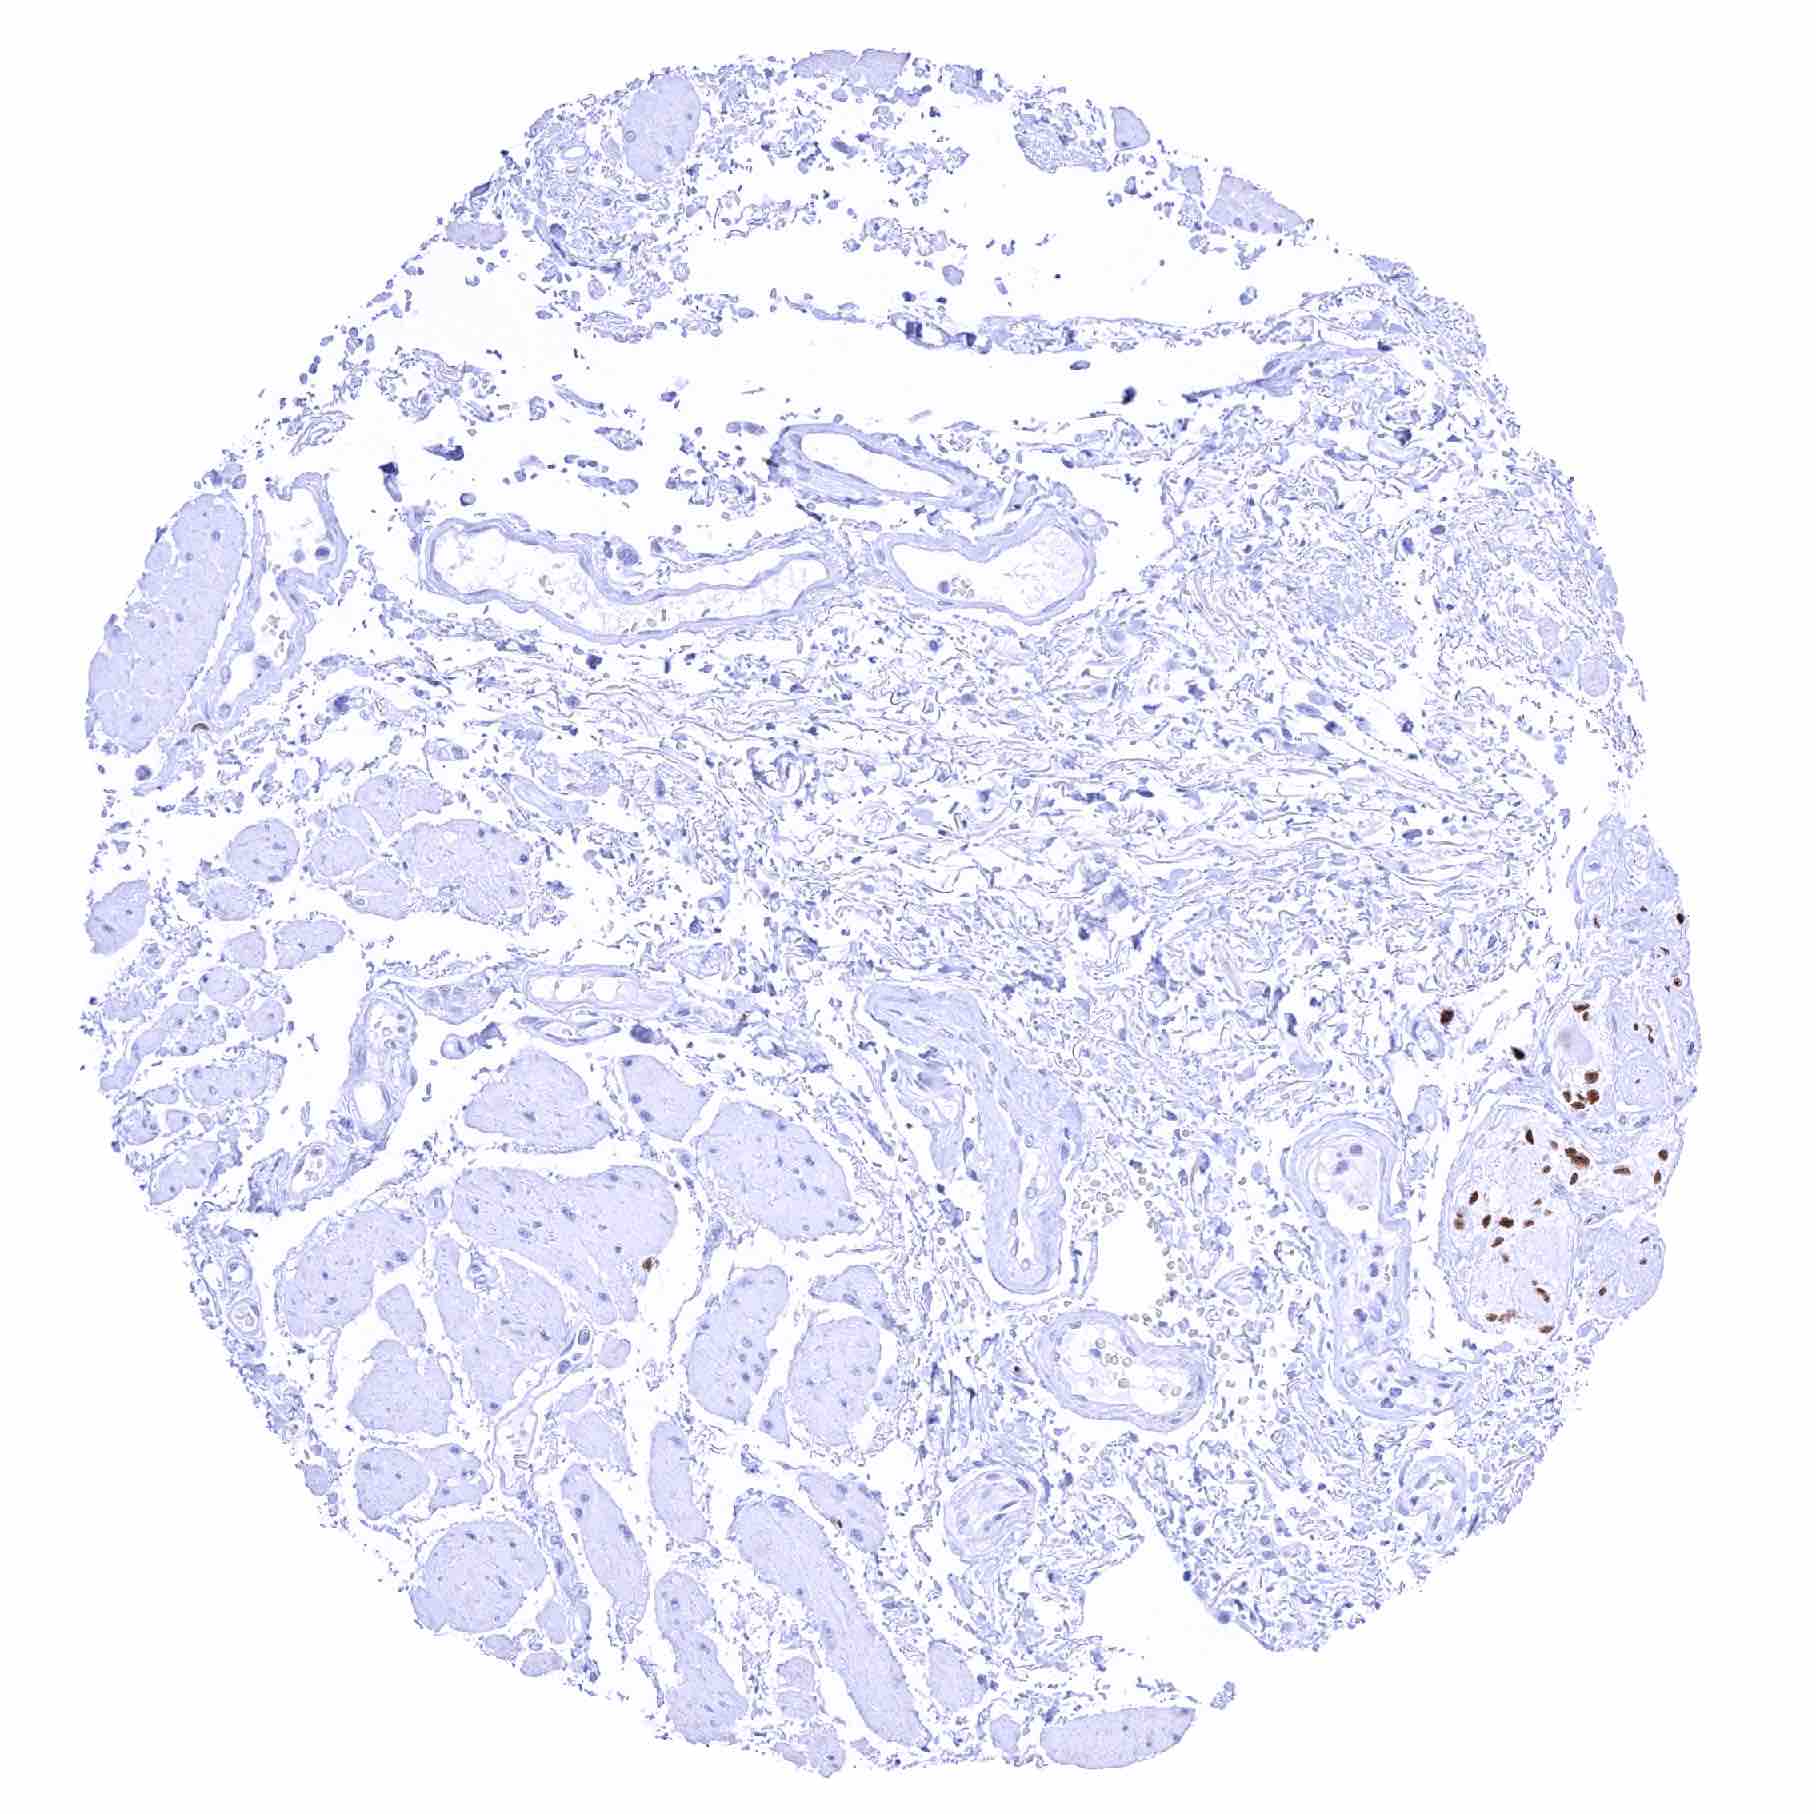

Prostate – Strong SOX2 positivity of a fraction of basal cells